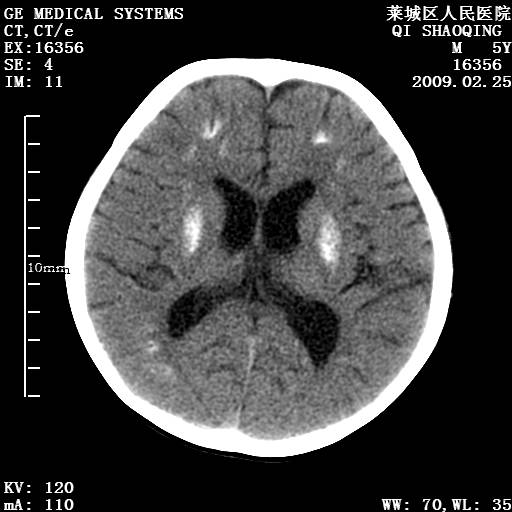

以下是引用wangzhengyuan在2009-2-28 10:22:00的发言:[br]甲状旁腺功能减退引起的脑改变.

以下是引用zsl6918在2009-2-28 10:17:00的发言:[br]首先考虑甲状旁腺功能低下所致,可结合实验室检查明确.另外需除外先天性宫内感染所致.

以下是引用余辉在2009-3-1 9:35:00的发言:[br]患者明显的肢体及智力改变,不支持fahr病,多考虑甲旁低,有可能伴有甲低(呆小症).进一步检查。